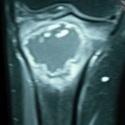

Des gonalgies révélatrices d’un lymphome de Burkitt

Faida Ajili, Imene Gharsallah

PAMJ. 2014; 18: 266. Published 01 August 2014